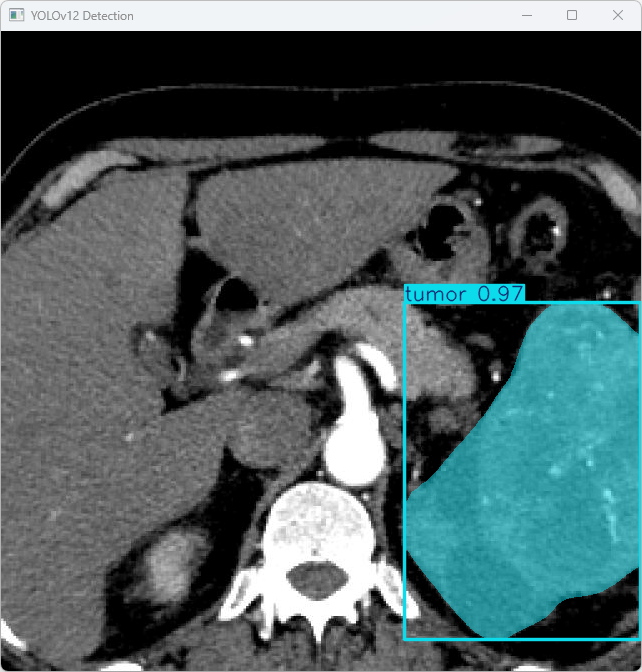

图15 YOLOv12 Detection Result

这张图展示了YOLOv12模型在医学图像(如CT扫描)中的应用,成功检测并标记了图像中的一个肿瘤区域。模型准确地识别出肿瘤,并标记为“tumor”,其置信度为0.97,表明模型对该区域的判断具有较高的可靠性。该图像的检测结果展示了模型在肿瘤区域识别中的高效性和准确性,能够为医生提供精确的定位和诊断支持。

YOLOv12模型在推理过程中表现出良好的速度和高效性,能够快速且准确地识别医学图像中的肿瘤区域,置信度为0.97,表示对检测结果有较高的确定性。此外,模型的处理速度也较为迅速,适合在医学影像分析中使用。